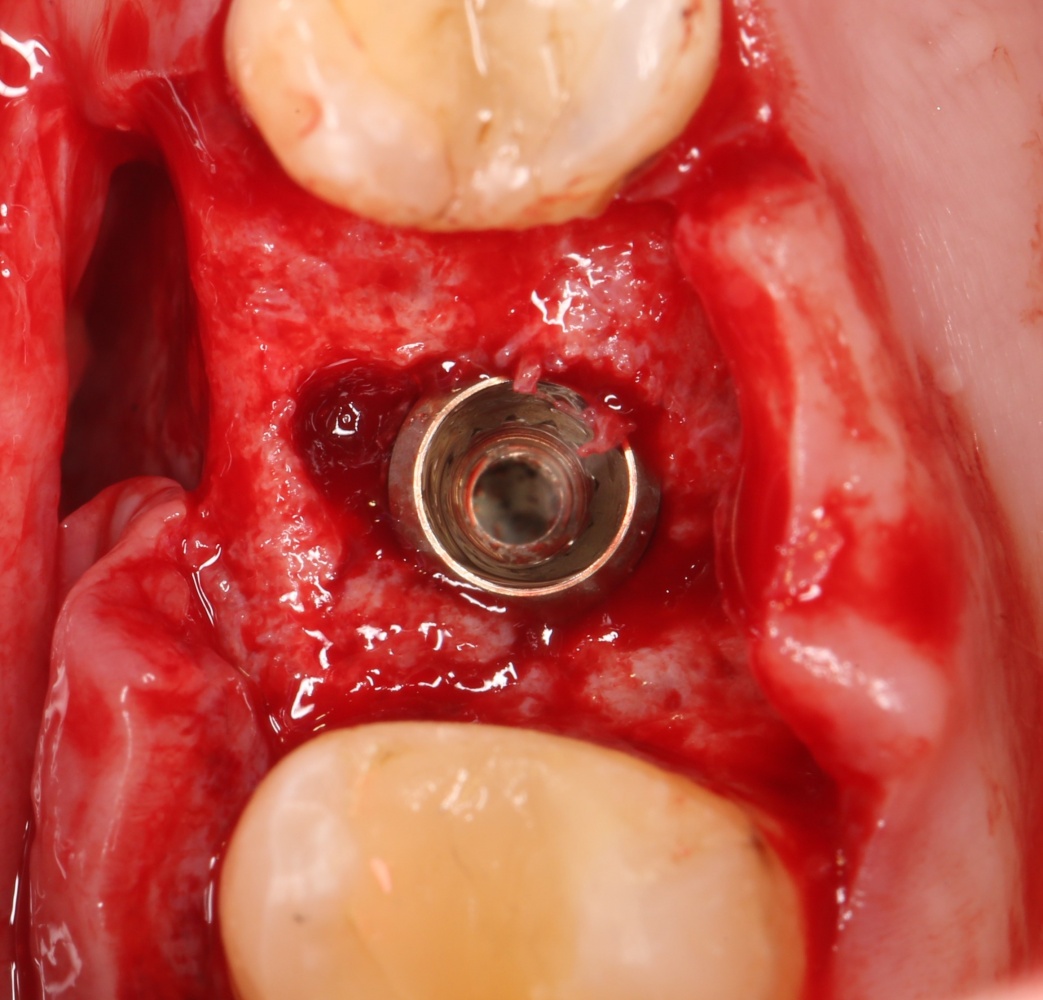

Вот клиническая картина через 4 месяца после ранее проведенной имплантации с остеопластикой:

Ну хорошо. Швы сняли. Делаем разрез. Обрати внимание, что после всех проведенных операций у нас остается очень небольшой по ширине слой жевательной слизистой оболочки:

Устанавливаем формирователи десневой манжеты. Сегодня я называю эту процедуру не менее важной, чем любой другой этап имплантологического лечения:

Если честно, то сейчас бы я использовал другой шовный материал и другой тип швов. Одно неизменно, — и я об этом много раз говорил, — самая широкая часть формирователя десны должна находиться на уровне десны. Так, чтобы эффективно отрабатывать т. н. «биологическую ширину».